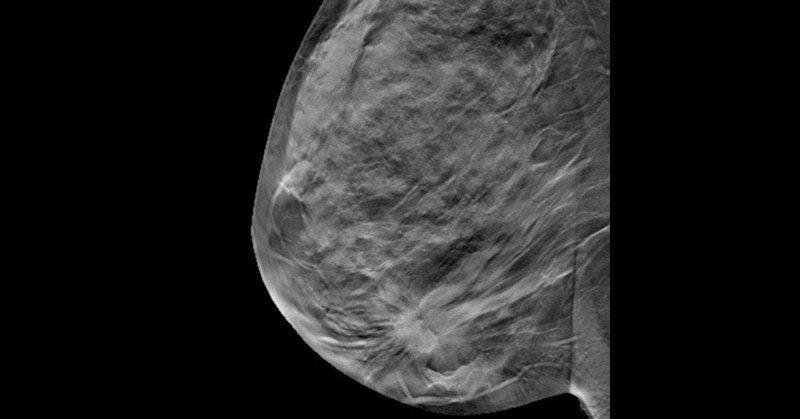

DBT screening reduced recall rates and improved specificity over digital mammography in women with a family history of breast cancer.

This cohort study compares the performance of digital breast tomosynthesis to conventional digital mammography in screening women with a family history of breast cancer.

📢📢The FIRST review on #DBT for #FamilyHistory #BreastCancer: Performance of Digital Breast #Tomosynthesis VS Digital #Mammography in Women With a Family History of Breast Cancer: A Systematic Review - Clinical Breast Cancer https://t.co/9CS6SMJo67

Digital breast tomosynthesis (DBT) provides reconstructed 3D mammographic images of the breast and is increasingly used in breast cancer screening and diagnosis. Several systematic reviews and...